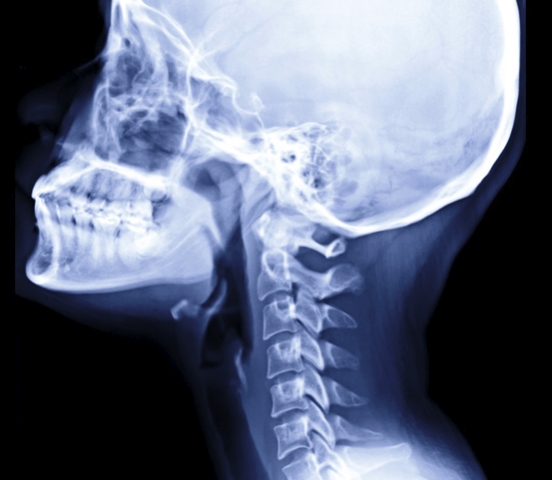

뒷목은 머리 뒤쪽에서 어깨로 이어지는 부위로, 경추(목뼈), 주변 근육, 신경이 밀집한 곳입니다. 이 부위는 머리를 지탱하고 움직이는 역할을 하며, 신경과 혈관이 몰려 있기 때문에 작은 이상에도 뒷목이 뻐근한 증상 통증이나 불편함이 쉽게 발생할 수 있습니다. 현대인의 생활 방식과 맞물려 뒷목 통증을 호소하는 사람들이 많아지고 있습니다.